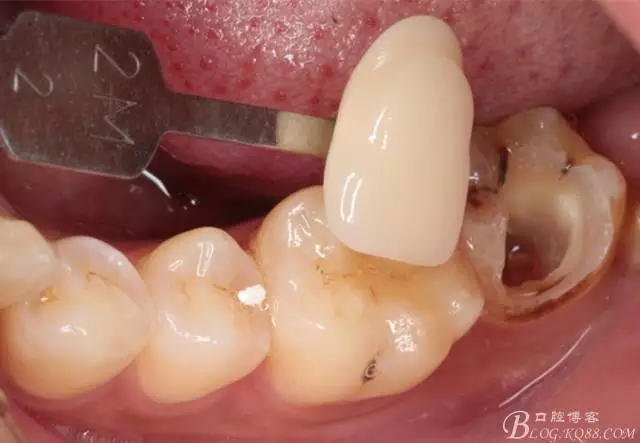

流動(dòng)樹脂充填窩洞,金霸王車針和鎢鋼車針常規(guī)備牙,配合硅膠尖拋光,頰側(cè)排00排齦線。硅橡膠二次法取模,記錄咬頜關(guān)系,臨時(shí)樹脂充填窩洞。